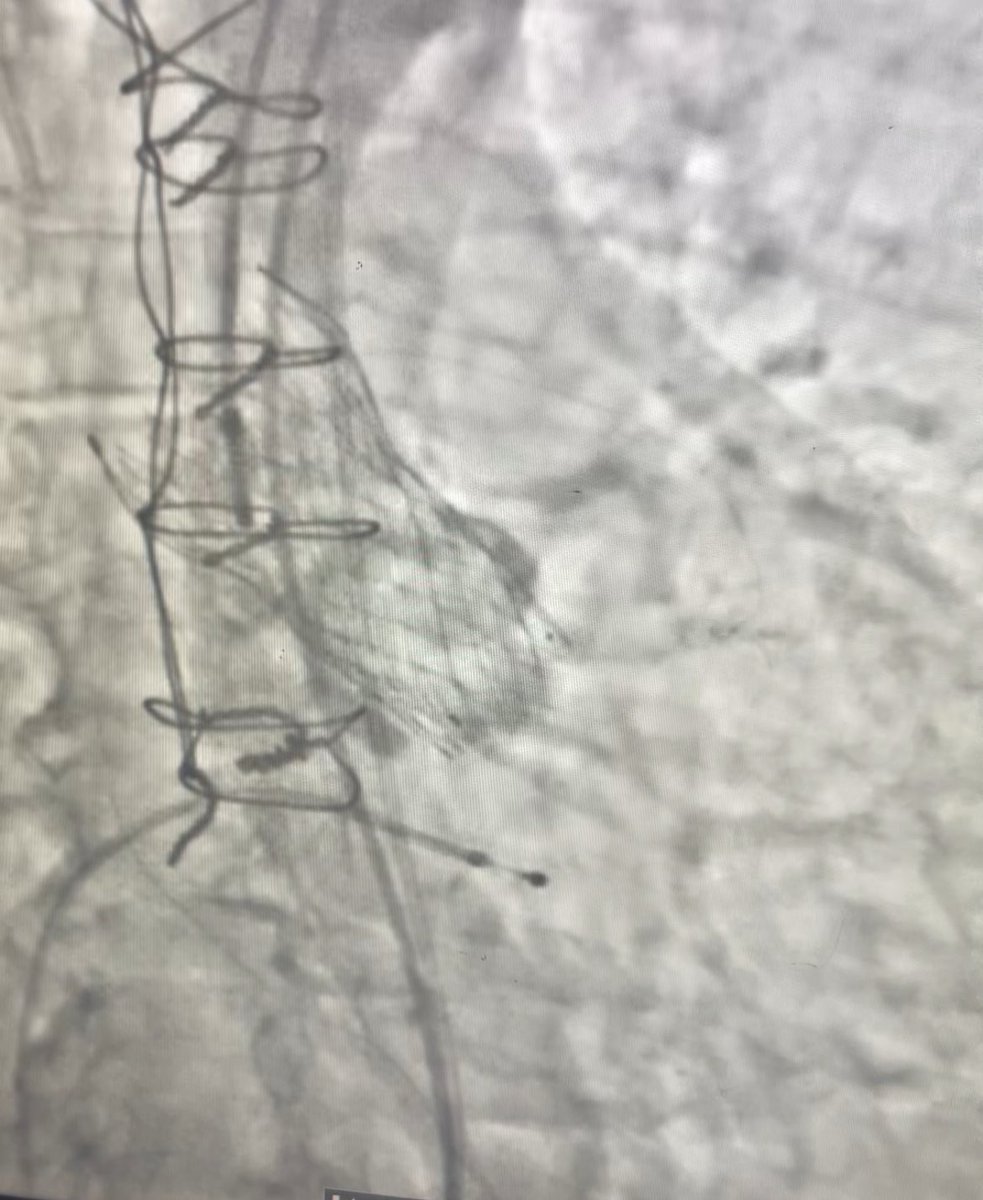

LAMPOON for TMVR valve in valve. Base to tip split. Implanted a 29mm S3 valve. #TMVR #TAVR #safeTAVI #Mumbai